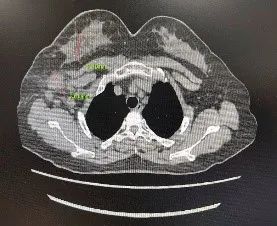

CT:提示右侧乳房未见明显的肿块,右侧腋窝淋巴结明显肿大;

图2. 胸部CT 2021.9.25